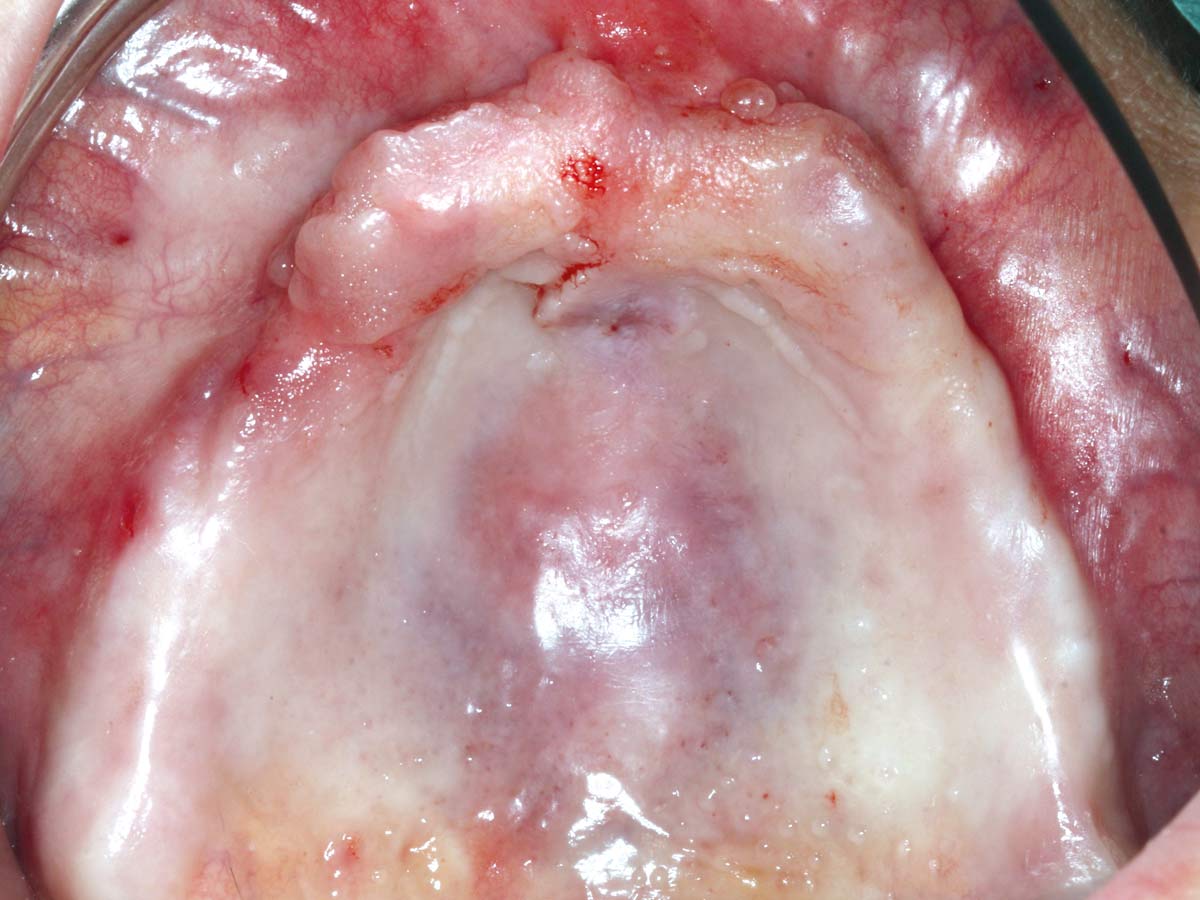

1/23 - Treatment overview – implant planning

Full arch reconstruction of the maxilla with maxgraft® bonebuilder - Dr. M. Erbshäuser